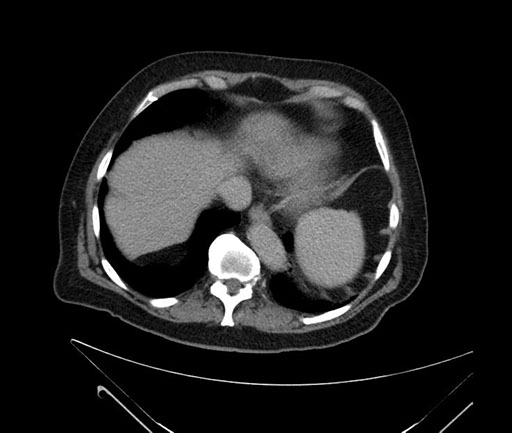

Axial - 3 months prior